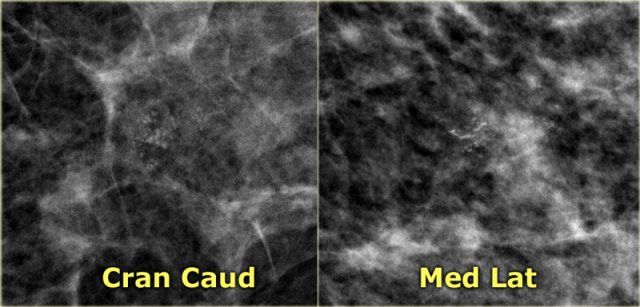

Milk of calcium Milk of calcium

On the craniocaudal image the calcifications are round, fuzzy and ill-defined.

On the mediolateral view the calcifications appear as semilunar, crescent shaped tea cups.

Click on the image for an enlarged view.